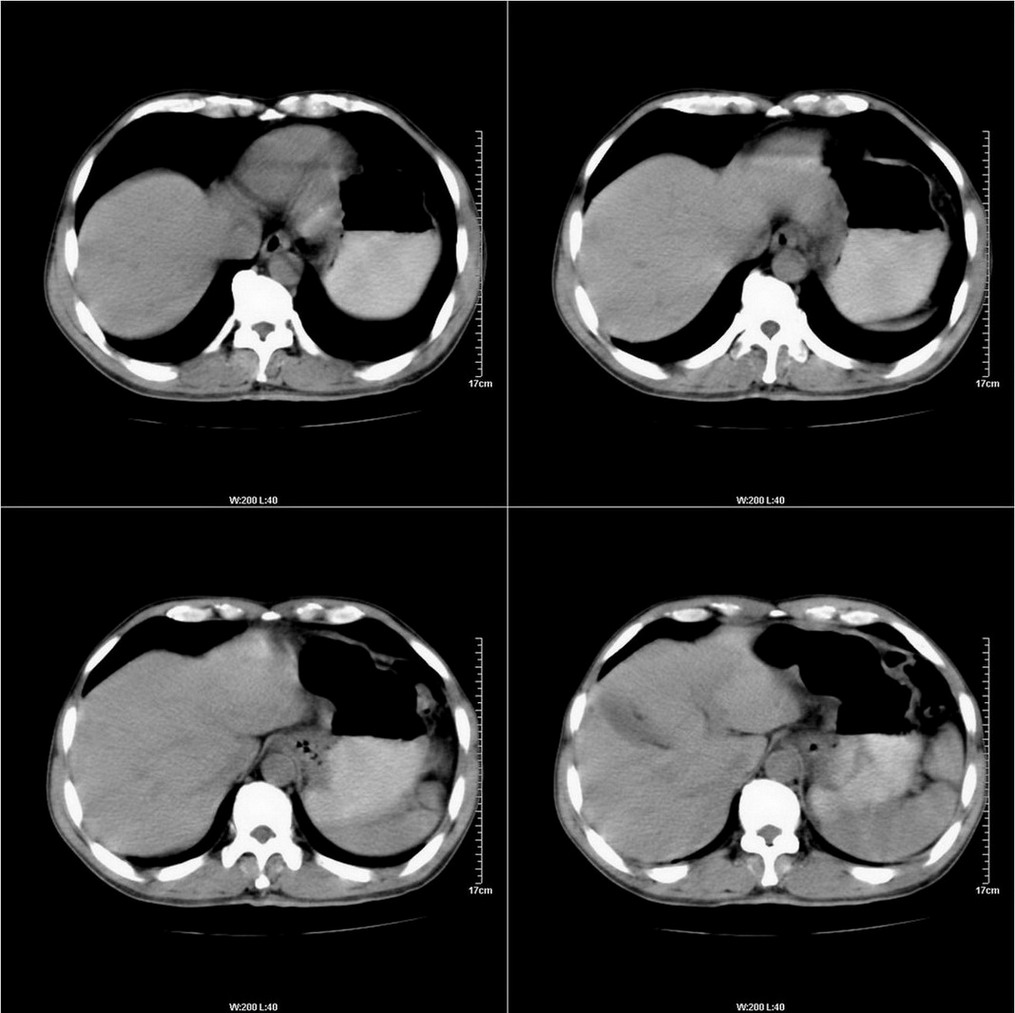

标题: CT14220:男性,59岁。腹部疼痛不适半年余。 [打印本页]

标题: CT14220:男性,59岁。腹部疼痛不适半年余。

建议结合胃镜或钡餐检查,考虑胃底贲门癌可能性大。

考虑:1、肝右叶下部小囊肿;

2、胃可能为准备充盈不良所致,必要时请胃镜进一步检查。